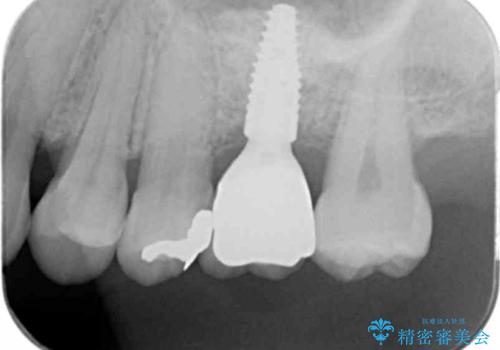

最終的な歯の位置を矯正の担当医と綿密に相談しながら、インプラントの埋入部位を決定し治療にあたりました。

骨量が少なかったことから、上顎洞内へのソケットリフト方をインプラント埋入と同時に施行しています。

- 51.4万円(ストローマンインプラント・ソケットリフト・仮歯・カスタムアバットメント・ジルコニアクラウン)費用は治療当時の料金となります

矯正治療により最終的な歯のポジションは動いてしまうことからインプラント埋入部位を綿密に検討する必要があります。